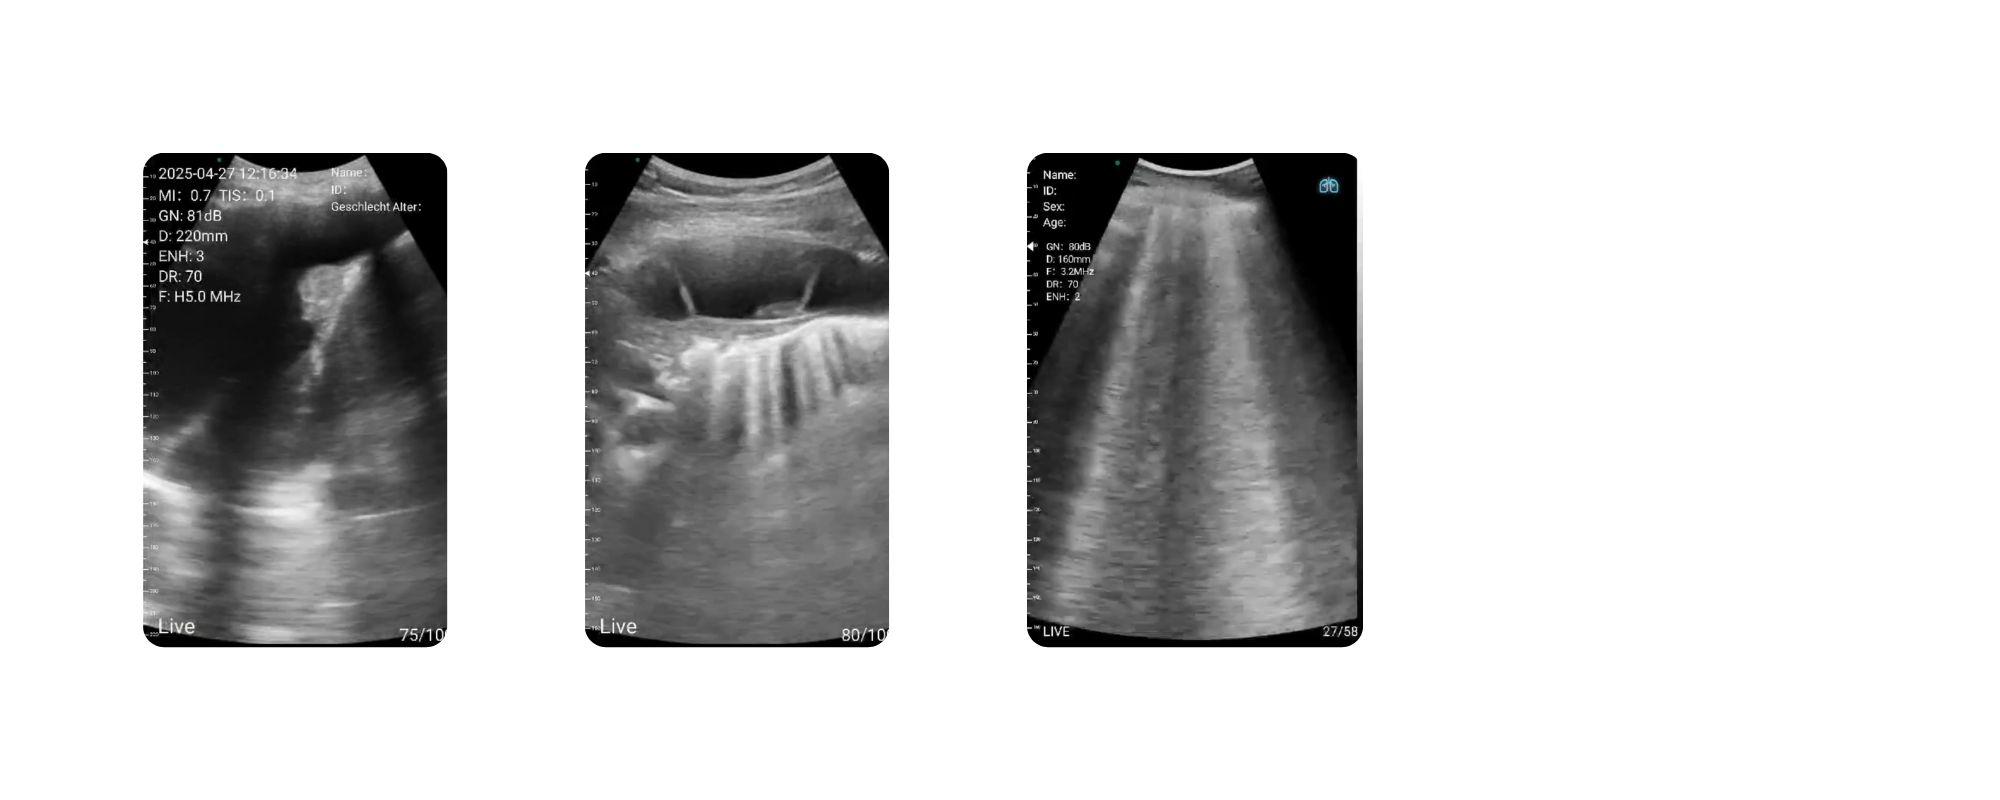

سونوگرافی ریه (LUS) برای تشخیص افیوژن، خطوط B، پنوموتوراکس و بررسی وضعیت تنفسی

1. پزشکی عمومی و اورژانس

در پزشکی عمومی و اورژانس، سرعت تشخیص حیاتی است. CLP4 در موارد زیر عملکرد برجستهای دارد:

-

بررسی شکایات حاد شکمی مانند آپاندیسیت، کولیک، درد پهلو

ارزیابی علائم ریوی مانند پنوموتوراکس، افیوژن پلور

بررسی تروما (FAST Exam)

سنجش وضعیت هیدراتاسیون با ارزیابی IVC

تشخیص سریع خونریزی داخلی یا تجمع مایعات

5. عضلانی–اسکلتی (MSK) و طب فیزیکی

برای معاینات عمقی و سطحی عضلات و مفاصل، سونوگرافی هندهلد CLP4 گزینهای ایدهآل است:

بررسی تاندونها (Rotator cuff، Achilles، Patellar)

بررسی لیگامانها، پارگیها و التهابها

ارزیابی هماتوم یا تجمع مایع

بررسی عضلات سطحی و عمقی

کمک به تزریقهای دقیق (Guided Injection)